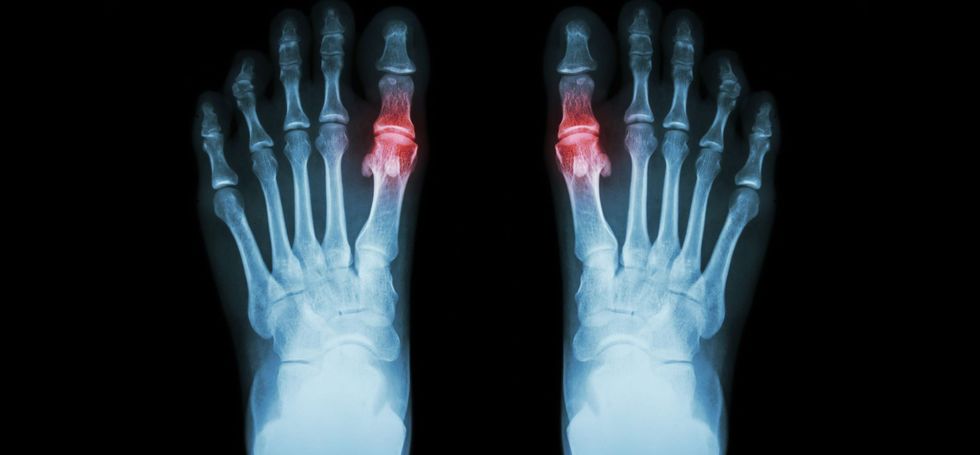

Shpërthimi i tij para moshës 30 vjeç, është një formë e rrallë dhe zakonisht lidhet me ndonjë çrregullim enzimatik që shkakton mbiprodhim të purineve ose mund të jetë pasoj e sëmundjeve të veshkave. Në 85–90% të rasteve, ataku fillon në një artikulacion dhe atë në artikulacionin e parë metatarsofalangeal të gishtit të madh të këmbës (Podagra).

Në 3-14 % të rasteve, përfshihen më shumë artikulacione (nyje) dhe sipas shpeshtësisë, artikulacionet që preken më shpesh janë tallokruralët (nyjet rrënjës së shputave), gjunjët, radiokarpalët (nyjat e rrënjës së shuplakave), gishtat dhe bërrylat.

Depozitimi i urateve me pasojë artritin urik, haset shpesh në artikulacionet (nyjat) e dëmtuara më parë si në nyjat Heberden (janë ënjtje të nyjave të gishtave të shuplakave). Në shumicën e rasteve, ataku fillon shpejtë, me ënjtje, skuqje dhe nxehtësi të nyjës.

Radiografitë (incizimet me Rëntgen) e bëra gjatë fazës akute, evidentojnë vetëm edem (ënjtje) të indeve të buta, pa ndryshime në kocka apo në artikulacione (nyje). Ndryshimet tipike radiografike që shihen në fazën kronike janë erozionet (gërryerjet) në nyje, me buzë sklerotike (të forta), të cilat duken me shfaqjen e tofeve. Mirëpo, këto ndryshime, vështirë mund të diferencohen nga erozionet në artritin rheumatoid.